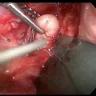

Minimally invasive VATS enucleation of a proximal esophageal leiomyoma is a safe approach to treat this unusual benign esophageal tumor.